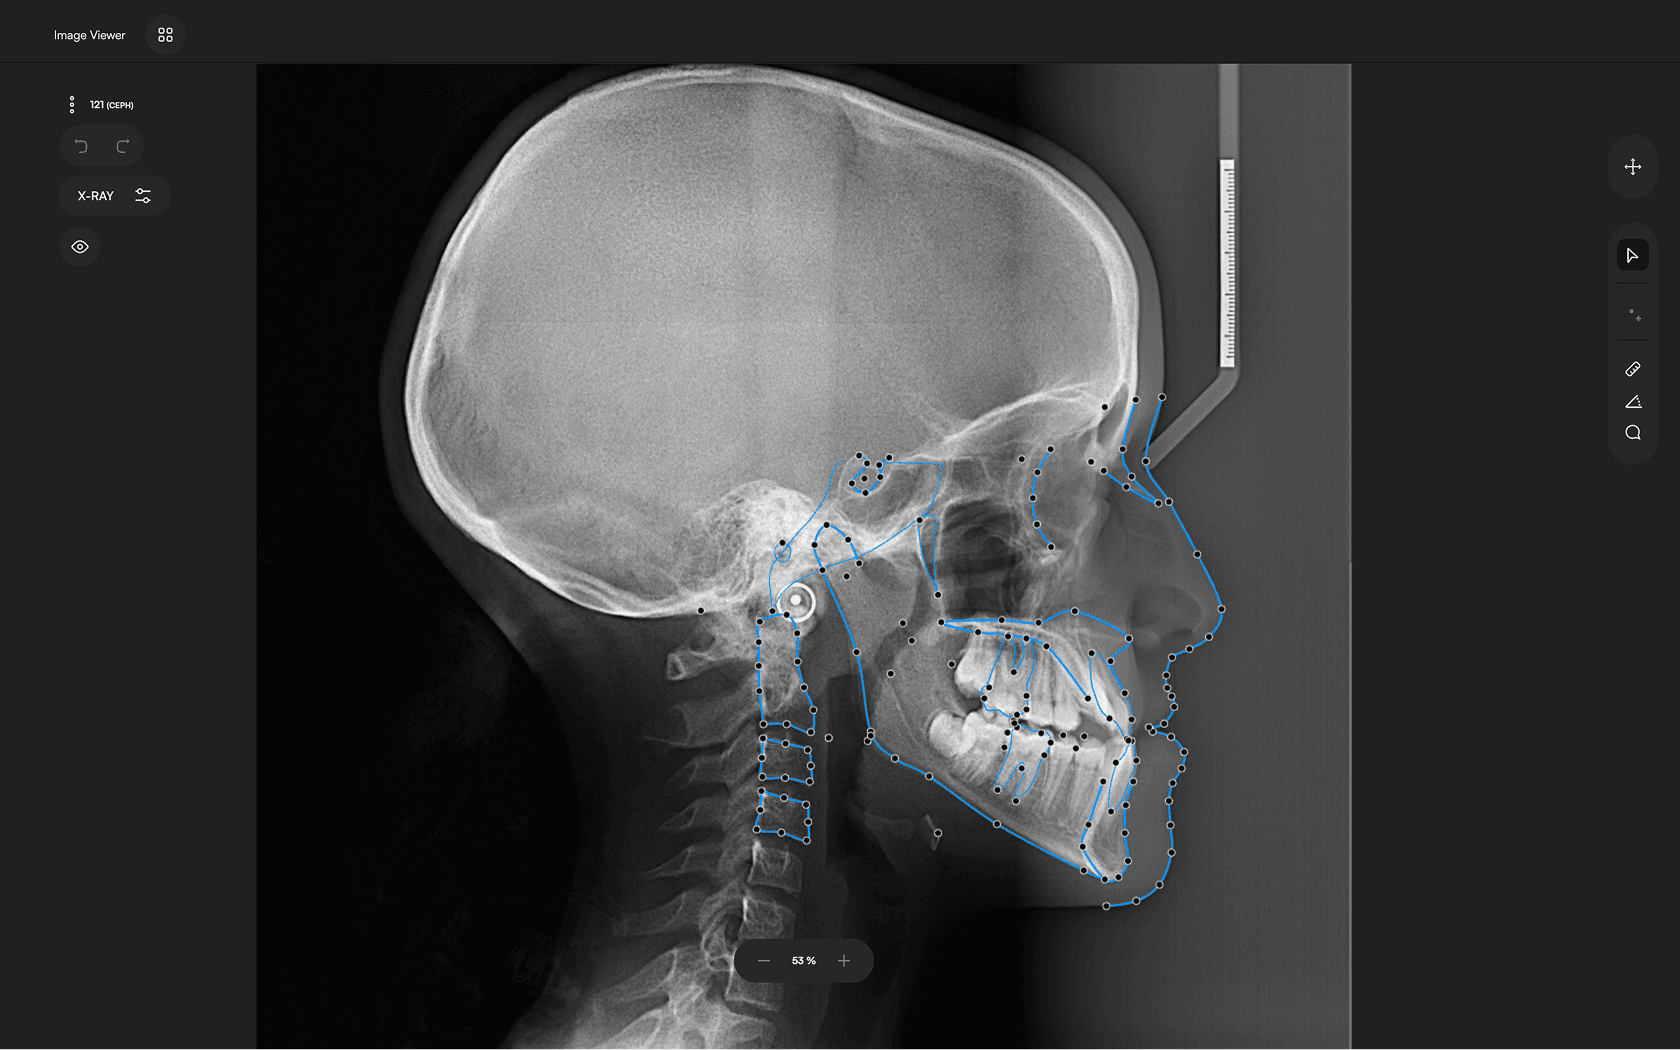

AI-driven Automated Lateral

Cephalometric Tracing

150+ landmarks traced in seconds

Identify 150+ orthodontic landmarks in under 10 seconds — a task that

traditionally may take more than 30 minutes.

Experience a comprehensive assessment of skeletal, dental, and soft tissue discrepancies.